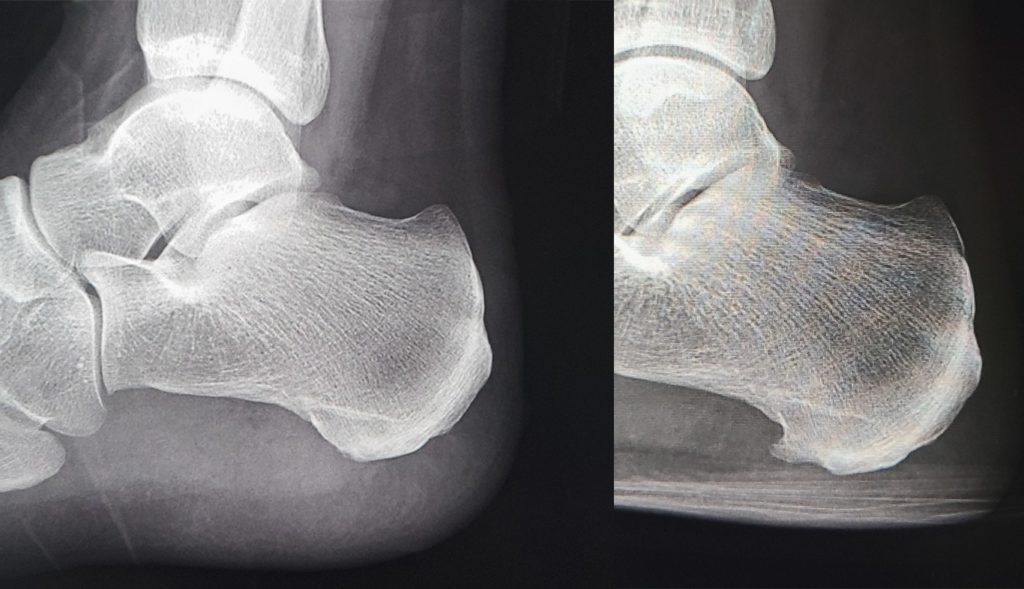

2021年の小規模な研究では、衝撃波療法が足底筋膜炎の効果的な治療法であることが示唆されています。研究者らは、4回の衝撃波療法が足底筋膜の厚さを減らすのに役立つことを発見した。また、その部分の炎症の症状も軽減されました。

2021年の研究によると、足底筋膜炎に対する衝撃波療法は一般に効果的な治療法であると考えられています。しかし、幅広い結果は、それがすべての人に効果があるわけではないことを示しています。